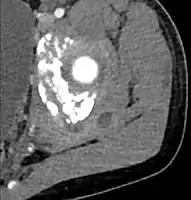

CT exam showing a multiloculated fluid collection in the left gluteus minimus muscle found to be a staph aureus pyomyositis in a 12-year-old healthy boy.